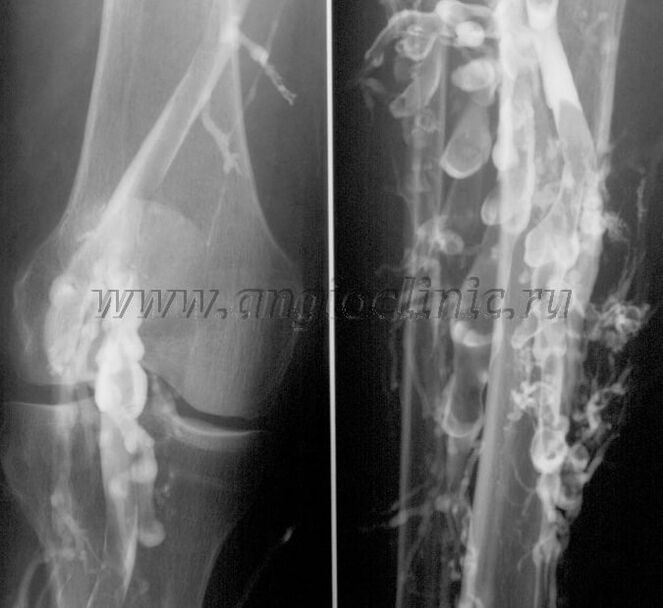

Kontrastna venografija

Obično je ultrazvučno skeniranje dovoljno za potpunu dijagnozu venske patologije, ali u nekim slučajevima potrebno je proučiti odnos između stanja dubokog i površnog venskog sustava, osobito u slučaju recidiva proširenih vena i sekundarnih proširenih vena.

Za rješavanje ovih problema koristi se kontrastni rendgenski pregled. Vene safene se punktiraju i daje kontrast. Na monitoru rendgenskog aparata prati se kretanje kontrasta te se provode svi potrebni testovi i projekcije. Trenutno se venografija za varikozne vene koristi vrlo rijetko.